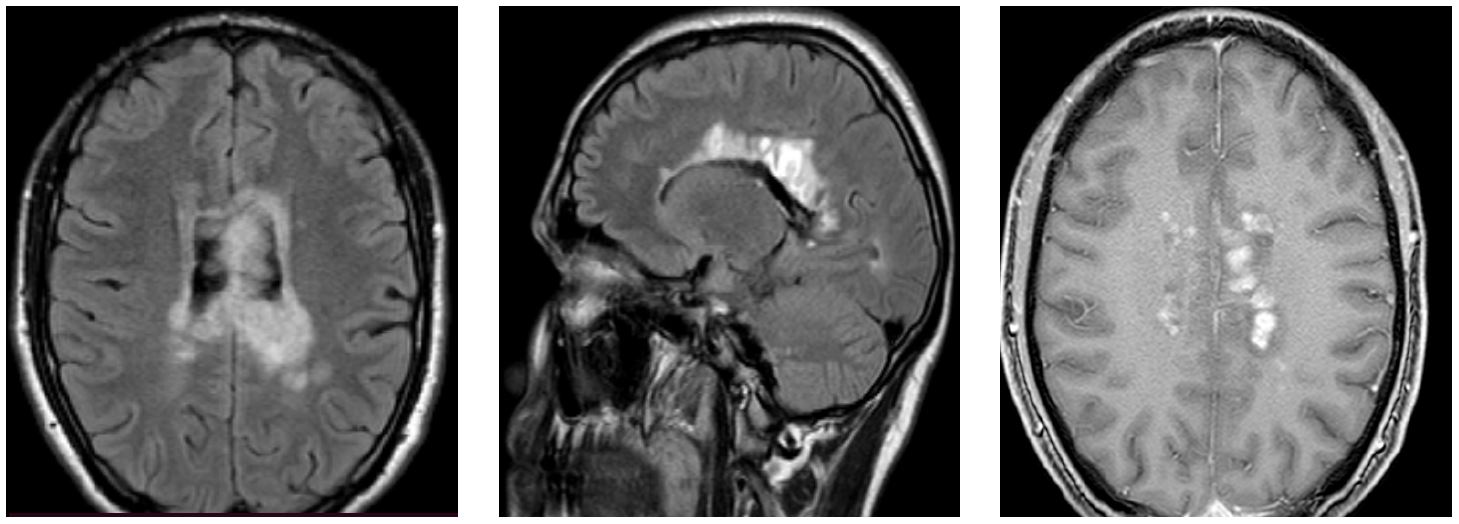

Рис. 2. МРТ-изображения в режимах T2 ВИ и FLAIR, 20.05.2020

Новое обострение с середины мая 2020 г. – усиление шаткости, появились речевые нарушения – 2-е многоочаговое обострение за 4 месяца заболевания с отрицательной динамикой по МРТ (рис. 2).

– 20.05.2020: головной мозг – ОРЭМ? Резко отрицательная динамика по количеству очагов, срединные структуры смещены вправо на 2 мм, от 3 до 40 мм, с умеренным перифокальным отеком, с кистозной трансформацией крупных, повышение сигнала от хиазмы с увеличением ее объема. Компримированы боковые желудочки с перивентрикулярным отеком. После контраста – выраженное неоднородное усиление сигнала по периферии от большинства выявленных очагов;